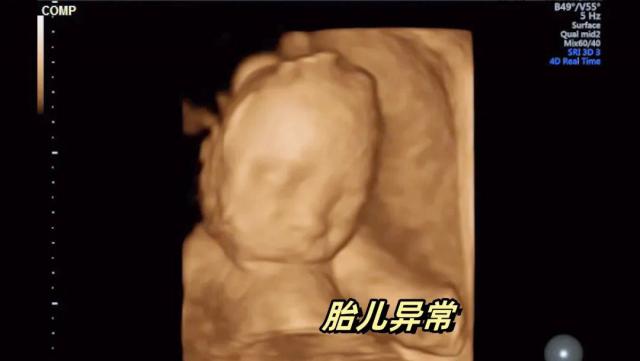

小美怀孕了,原来一家人还挺幸福的,可是她怀孕七个月大的时候,发现胎宝有问题。

大夫的话就像冰冷的刀刃,扎进了孕妈小美的心里——”儿童先天性发育不全,手脚有问题。"

大夫建议“引产”,宝宝到底留不留,小美的心里充满了矛盾和挣扎。